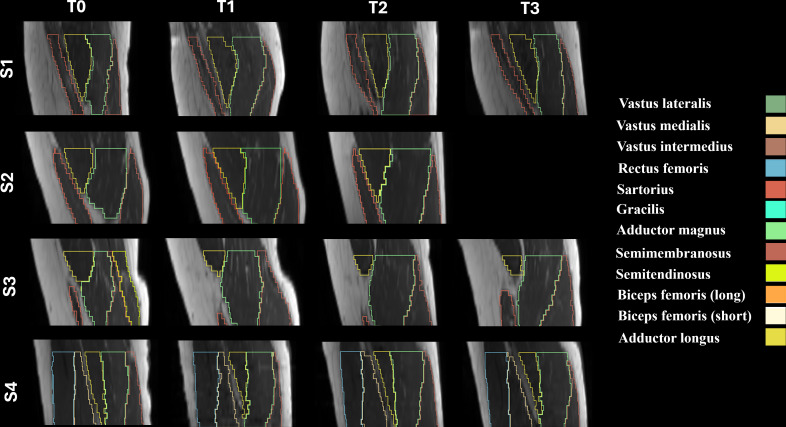

Methods: Four male participants with chronic SCI underwent a 6-month FES-cycling training program, consisting of two 30-minute sessions per week. MRI scans were performed at baseline (T0), after 3 months (T1), at the end of the training (T2), and 1-month posttraining (T3). The MRI protocol included T1-weighted imaging for volume quantification, Dixon imaging for fat fraction, multi-echo spin echo for T2 relaxation times, and diffusion tensor imaging to assess diffusion parameters.